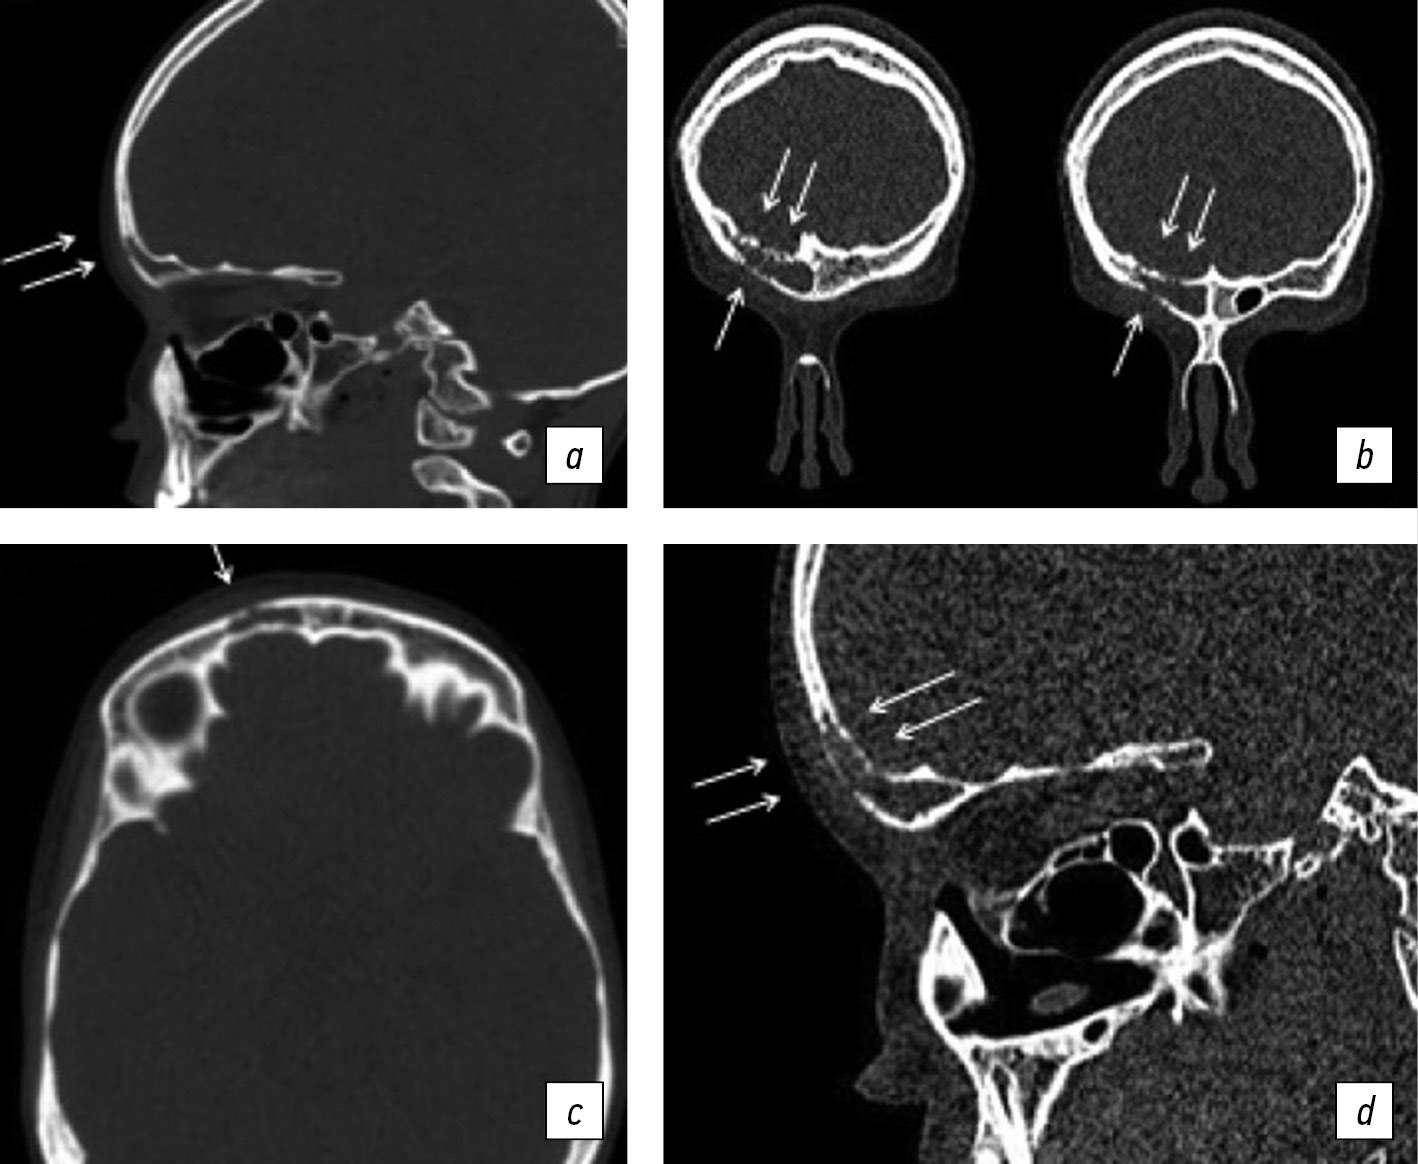

The first CT scan of the facial skull revealed a local disruption of the integrity of the anterior wall of the frontal sinus with a length of 2.5 mm (foci of destruction?) with total shading of the frontal sinus chamber and partial reduction of the pneumatization of the lattice bone cells (Fig. 3a, b).

Fig. 3. Computed tomography of the facial skull: a, b, at the time of the first treatment; c, d, 2 weeks later (data from the Research Center’s archive). Arrows indicate destructive changes

Laboratory examination showed an elevated COE level of 23 mm/h (according to Westergren), whereas the other indicators were within the reference values. The CRP level was <5 mg/L. The child’s facial skull underwent destructive changes caused by undifferentiated skeletal disease and an increased antinuclear factor titer. To exclude granulomatosis with polyangiitis, the laboratory study was supplemented with an analysis for antineutrophil cytoplasmic antibodies (ANCA) of the IgG class. Because of the suspected injury, the child was referred to an ENT specialist and a maxillofacial surgeon. Despite 2 weeks of treatment by the ENT specialist, including a course of antibacterial therapy, no improvement in the child’s condition was noted. All of the previously mentioned symptoms, including subfebrile fever, persisted. A follow-up CT of the facial area was performed.

The second CT scan of the facial skull revealed negative dynamics, with an increase in the area of bone destruction in the anterior wall of the right frontal sinus and appearance of destructive changes in the posterior wall. The content of liquid density in the presence of dense inclusions (sequesters?) was visualized in the cavity of the right chamber of the right frontal sinus. The conclusion was a destruction of the chamber walls of the right frontal sinus (osteomyelitis), which represented a negative progression when compared with the previous CT data (Fig. 3c, d).